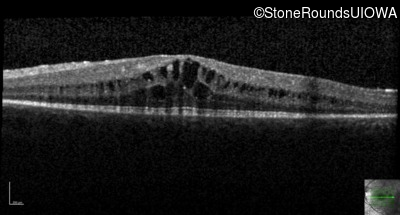

Optical Coherence Tomography - Left - 20/32

Exemplar / OCT Stack

OCT Stack